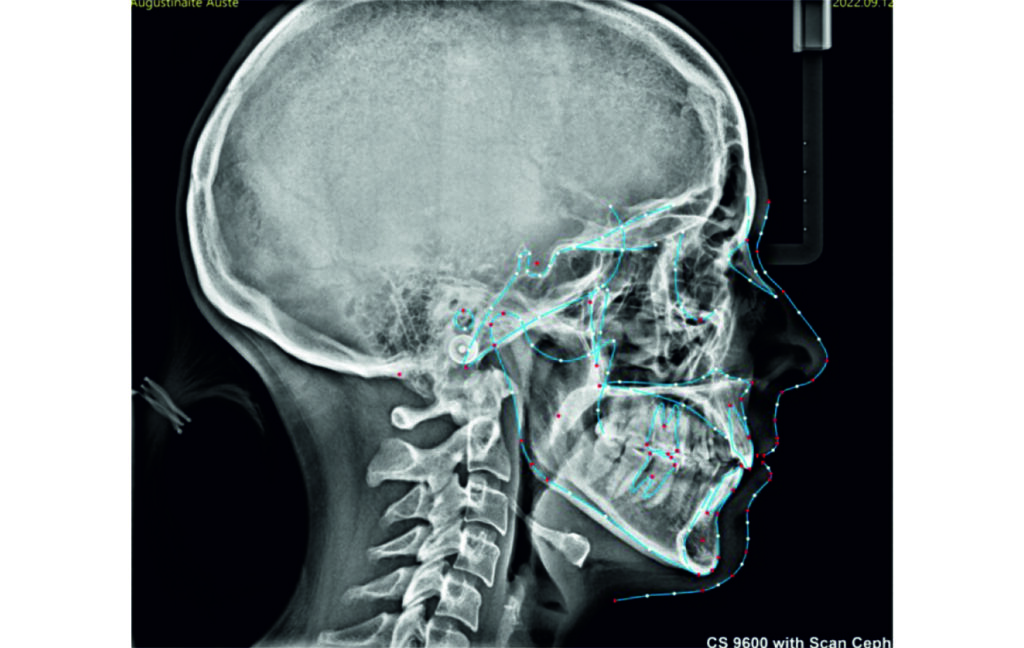

Initial Photos and datas

Angle Class II 2mm on the right, Angle Class II 2mm on the left, light mandibular asymmetry to the right, lower central line 1mm to the right, upper central line 1,5mm to the left, 1mm overjet and overbite. Sagittal asymmetry of upper dental arch. Light crowding upper and lower frontal segments, severe attrition of posterior teeth, night bruxism. Normal sagittal position of both jaws, high angle case, steep mandibular ramus,excessive lower facial height, open bite tendency.

Soft Tissue Analysis: convex profile, lower third of the face increased, slightly retrusive upper and lower lips, lip strain on closure.